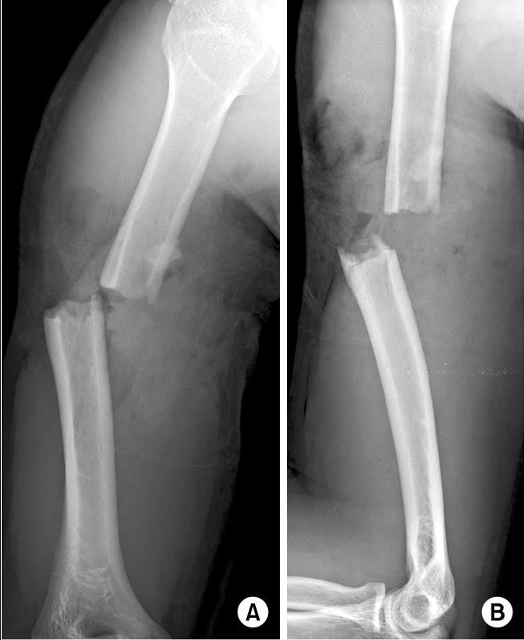

in the shown radiograph

1- what type of fracture

2- site of fracture

A

Spiral fracture of the mid shaft of the humerus